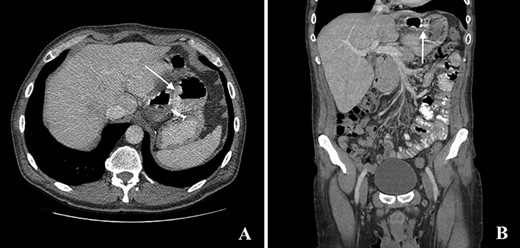

The computed tomography (CT) scan with oral contrast revealed a GGF (see Fig. 1). The upper gastrointestinal endoscopy confirmed a GGF and also demonstrated a stenosis of the gastro-jejunal anastomosis (GJA) (see Fig. 2).

Computed tomography with intravenous contrast images demonstrating a gastro-gastric fistula (arrows). A: axial reconstruction; B: sagittal reconstruction.